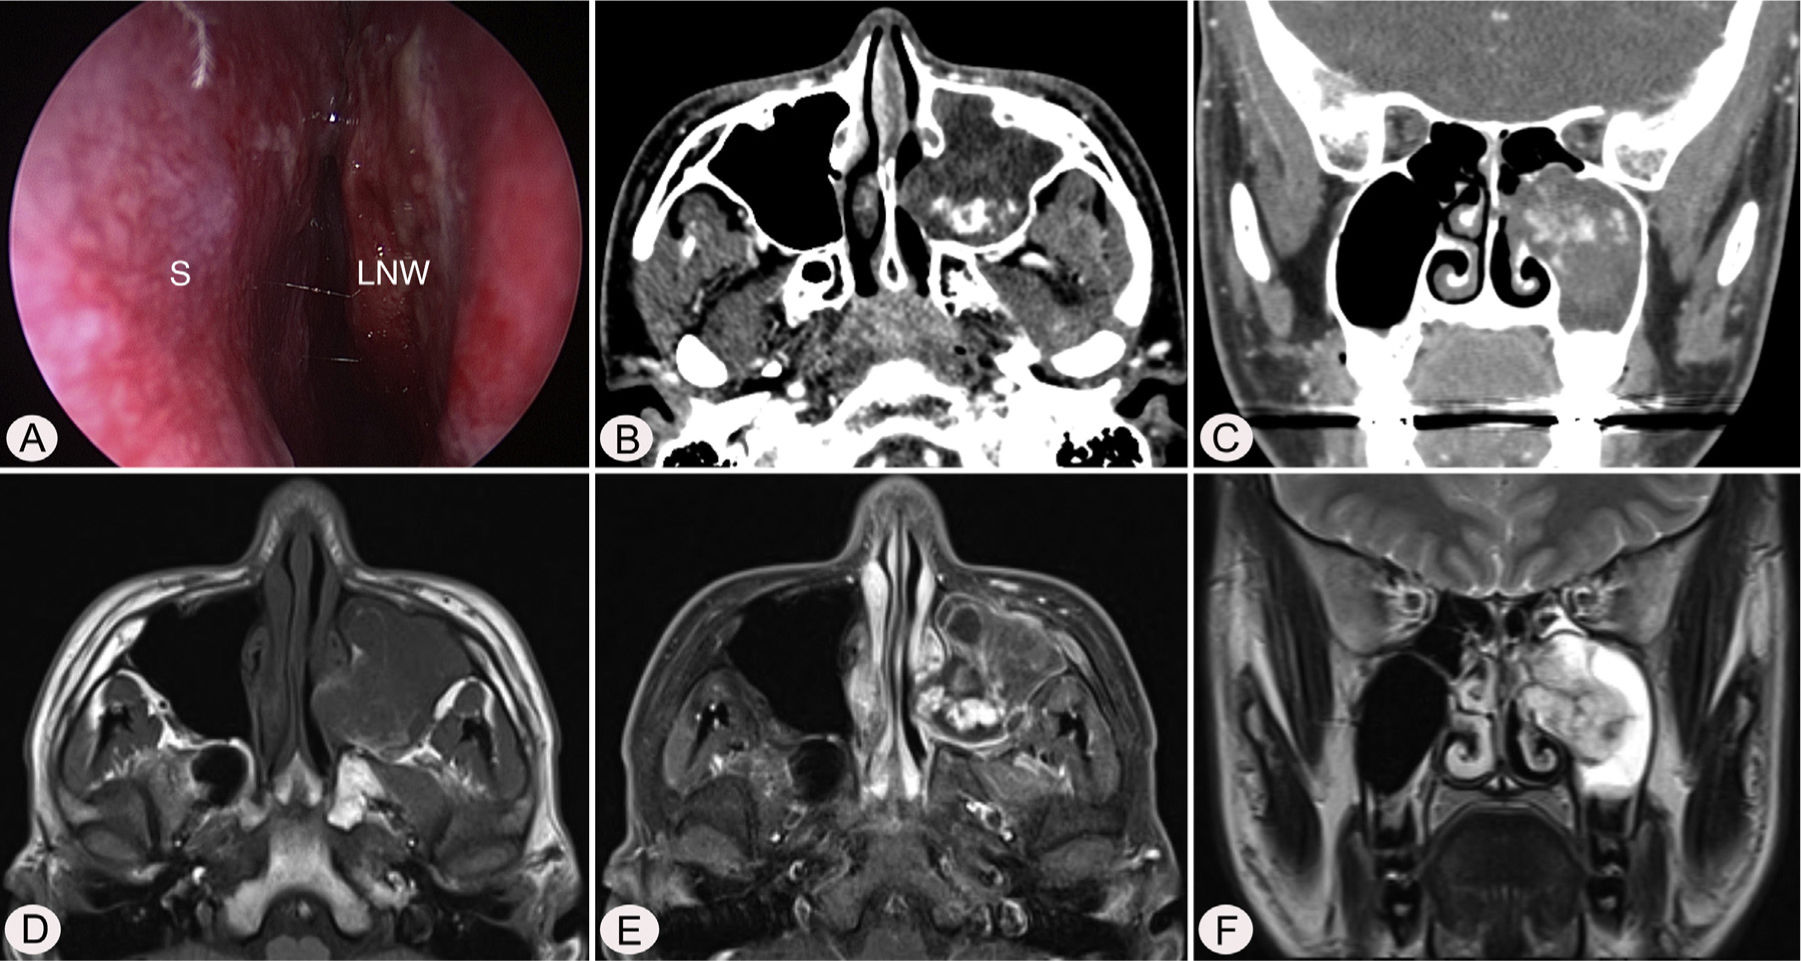

Case reportA 17-year-old male was referred to our outpatient clinic because of recurrent epistaxis after left nasal polypectomy. He had undergone nasal polypectomy due to nasal congestion at a local clinic 10 days ago. He had neither other symptoms nor any medical history. There was no history of trauma and no sign of allergy. The endoscopic examination revealed bulging of lateral nasal wall and bleeding due to left maxillary sinus mass (Fig. 1A). A Computed Tomography (CT) scan of the paranasal sinuses showed heterogenous enhancing mass in left maxillary sinus without adjacent bony involvement (Fig. 1B and C). On Magnetic Resonance Imaging (MRI), the mass expanding left maxillary sinus had mixed high signal intensity on T1-weighted images (T1WIs) and heterogenous high signal intensity on T2-weighted images (T2WIs) with an avid enhancement (Fig. 1D–F). Considering the location of tumor, surgical access was gained via Caldwell-Luc approach under general anesthesia because transnasal endoscopic sinus surgery had high risk of bleeding. The mass was originated from medial wall and partial superior wall of left maxillary sinus (Fig. 2A and B). The base of the lesion including the healthy mucosa around it was successfully removed with harmonic scalpel and microdebrider under direct visualization using a nasal endoscope and cauterized using suction cautery for prevention of recurrence (Fig. 3A). Histopathologic examination showed variable sized and irregular shaped vascular spaces with thrombus, consistent with arteriovenous malformation (Fig. 3B). Postoperative course was uneventful and he was discharged five days after surgery. Endoscopic examinations and CT performed 3 months postoperatively showed no evidence of recurrence.

Preoperative endoscopic and radiologic findings. Nasal endoscopy (A) shows bulging of left Lateral Nasal Wall (LNW). Axial (B) and coronal (B) computed tomographic images shows heterogenous enhancing mass in left maxillary sinus without adjacent bony involvement. The mass shows mixed high signal intensity on T1 axial (D), avid enhancement on postcontrast T1 axial (E), and heterogenous high signal intensity on T2 coronal (F) magnetic resonance images. S, nasal septum.

Although many arteriovenous malformations may be suspected clinically, imaging is required for confirmation and treatment planning, especially as incorrect diagnosis may lead to inadequate or inappropriate treatment resulting in life threatening hemorrhage as well as recurrence.7 MRI is the investigation of choice as it provides accurate information about the extent of the lesion, better contrast between the lesion and surrounding tissues, and has multiplanar capabilities. It can also help distinguish between the different types of vascular anomalies.2,8 Contrast-enhanced CT has a role in evaluating intraosseous lesions and the bony margins of extensive lesions that are under consideration of resection.2 Angiography, particularly digital subtraction angiography, has a specific but limited role in the diagnosis of vascular lesions, but should not be used as a first line investigation. However, it is useful for mapping out the blood supply of the lesion and in the assessment of the characteristics of flow of arteriovenous malformations.2 Angiography is usually reserved for therapeutic endovascular interventions.